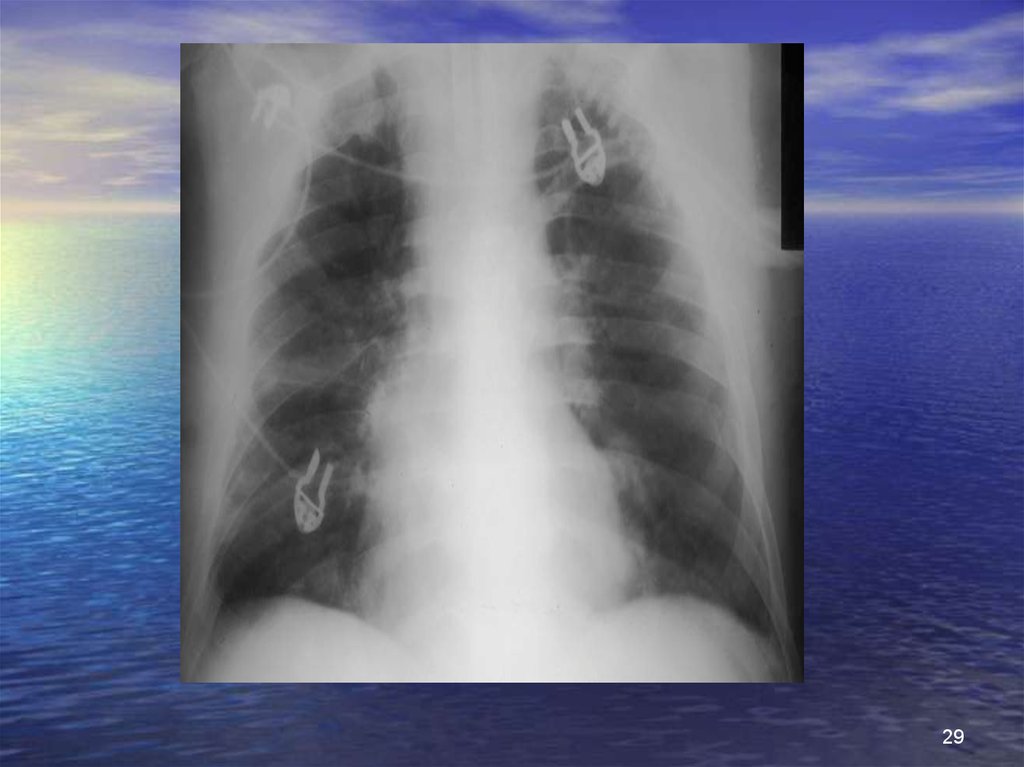

29.

29